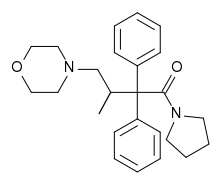

Ampromides

Structures

| Ampromides | ||||

|---|---|---|---|---|

|

|

| ||